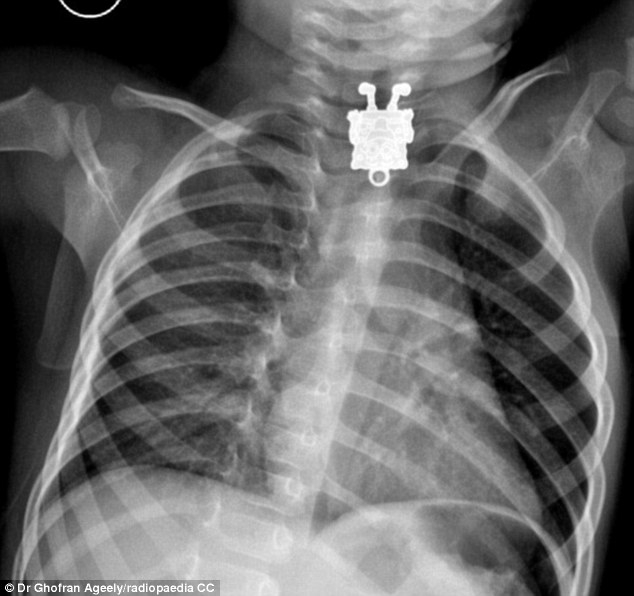

Buenas a todos, pues veréis muchas veces acabo inconscientemente con la pua en la boca, y pienso.. algún día sin darme cuenta me la trago.

Alguno le ha pasado, y si esta vivo puede contarlo?